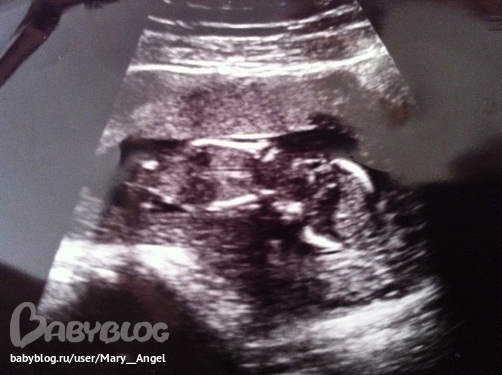

28 декабря мы были на первом скрининговом УЗИ, которое показало, что у нас всё в норме. И нам даже дали фотографию. Вот: